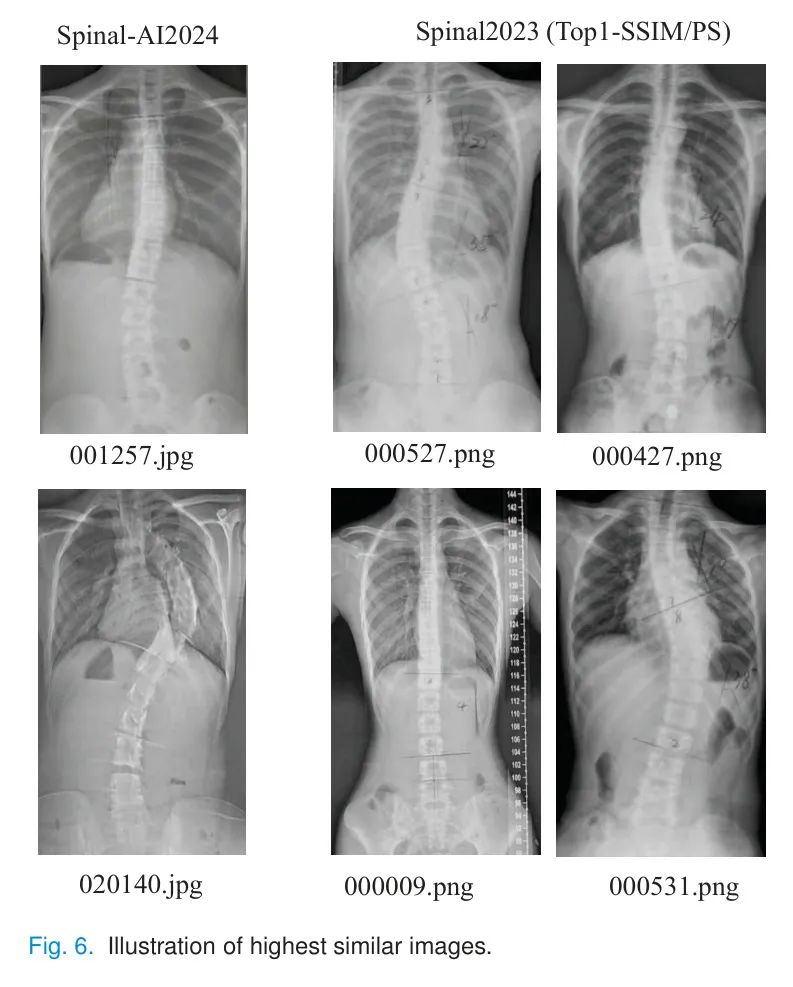

对于每个Spinal-AI2024图像,表7中呈现了前三项全面相似性审查,其中最相似的图像在图6中展示。结果显示,作者生成的数据集扭曲了原始标注,并产生了脊椎弯曲变化,这可以防止患者信息过度泄露。